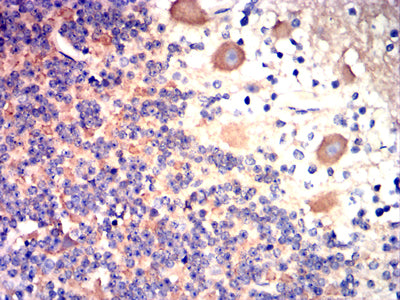

- Immunohistochemical analysis of paraffin-embedded human cerebellar tissues using BRAF mouse mAb with DAB staining.